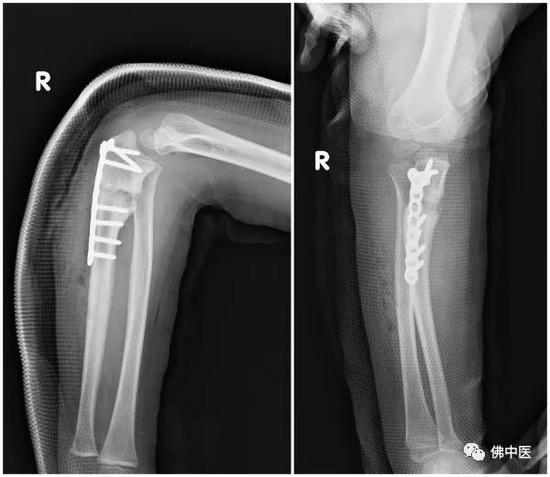

才巴术前右前臂全长侧位及正位X光

术前右前臂包肘侧位及正位

术后X光片